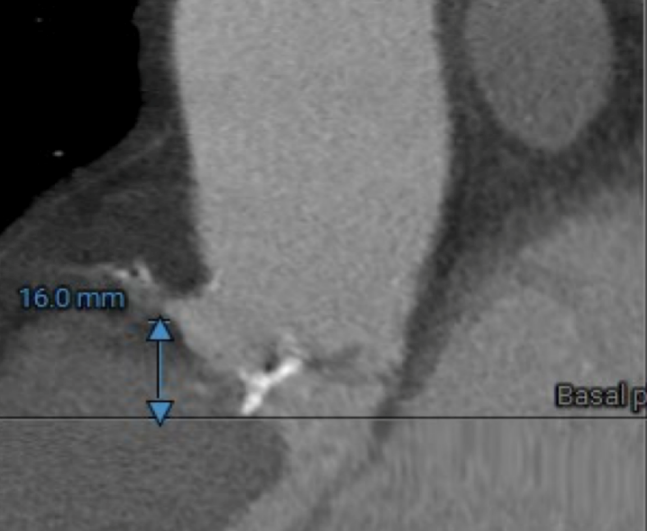

冠脉高度测量

LEFT CORONARY

左冠开口高度20.4mm

RIGHT CORONARY

右冠开口高18.8mm